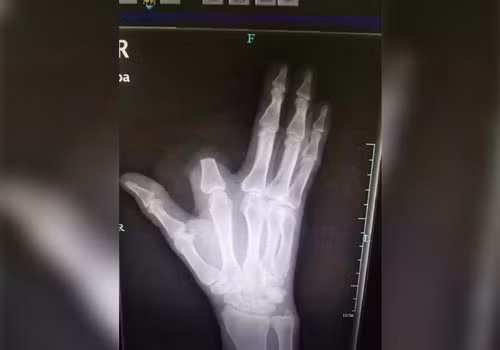

Trong lúc đang đốn củi trong khu rừng gần thôn ở thị xã Thượng Ngu, tỉnh Chiết Giang (Trung Quốc), ông Zhang vô ý bị một con rắn độc cắn trúng ngón tay.

Càng nghĩ càng hoảng hốt, ông vội vàng cầm rìu chặt bỏ ngón tay còn in dấu răng của con vật đáng sợ.

Tuy nhiên, vì cho rằng ngón tay bị đứt đã nhiễm độc tính nên ông đã vứt lại trong rừng. Chuyện đến nước này, các bác sĩ tại Bệnh viện Y học Cổ truyền Hàng Châu cũng đành lắc đầu chịu thua vì không có cách nào nối liền ngón tay với bàn tay được nữa.